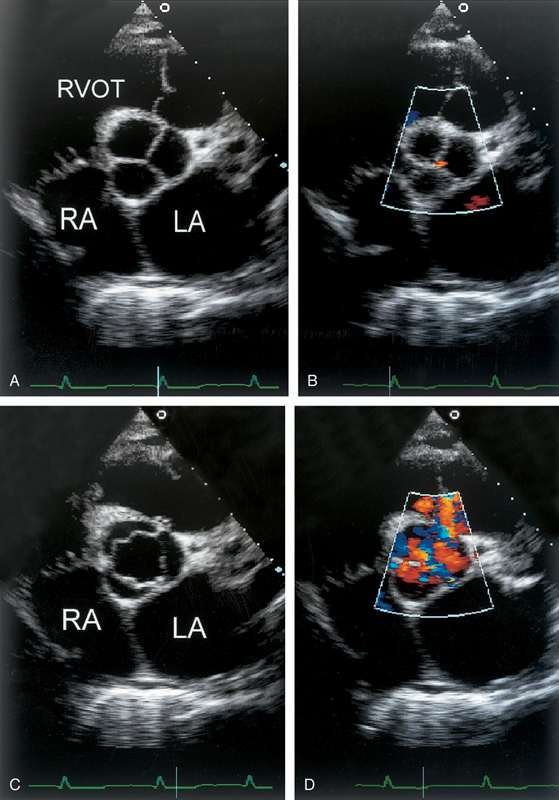

فحوصات تشخيصية لبعض امراض القلب والشرايين التاجية